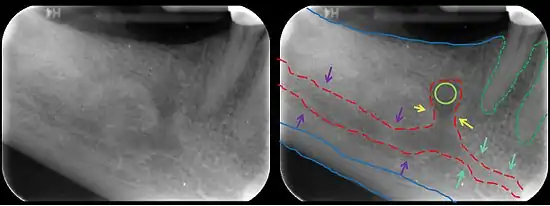

In human anatomy, the mandibular canal is a canal within the mandible that contains the inferior alveolar nerve, inferior alveolar artery, and inferior alveolar vein. It runs obliquely downward and forward in the ramus, and then horizontally forward in the body, where it is placed under the alveoli and communicates with them by small openings.

On arriving at the incisor teeth, it turns back to communicate with the mental foramen, giving off a small canal known as the mandibular incisive canal, which run to the cavities containing the incisor teeth.[1] It carries branches of the inferior alveolar nerve and artery.

The mandibular canal is continuous with tow foramina: the mental foramen which opens in the mental region of the mandible and carried the distal fibres of the inferior alveolar nerve as the mental nerve; and the mandibular foramen on medial aspect of ramus, into which the mandibular nerve enters to become the inferior alveolar nerve. The mandibular canal often runs close to the apices of the third molar tooth, and the inferior alveolar nerve can become damaged during removal of this tooth, causing sensory disturbance in the distribution of the nerve. This is sometimes the case for the second or first molar teeth, and care must be taken during removal or root canal treatment in such cases to prevent nerve injury or extrusion of root canal filling materials.[2]

Variations

Several variations of the mandibular canal exist with varying frequency. The most common variant is the retromolar canal (~10 % of canals), whereby a branch is given off in the mandibular ramus which terminates in the retromolar region of the mandible. The retromolar canal may cause bleeding during surgery in the retromolar region such as removal of mandibular third molar teeth. Other variants include a bifid canal with a branch (~41%):[3] following the course of the main mandibular canal before re-joining it (forward or buccolingual type); terminating at the apex of a tooth, usually the molar teeth (dental type); opening as an accessory mental foramen.[4] A trifid mandibular canal variation has also been described.[5][6]